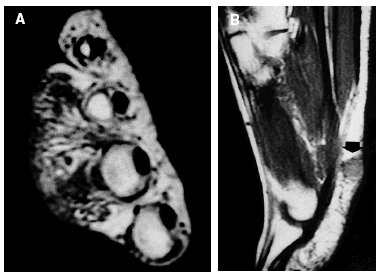

Fig. 1.--Resonancia magnética nuclear que muestra en A el caso 1: tumoración subcutánea infiltrativa, mal definida, de 5 cm en el dorso de mano. Y en B el caso 2: lesión plantar de 1,2 cm situada en hipodermis que contacta con fascia subyacente.

Fig. 2.--En A caso 2: situación del tumor en dermis profunda e hipodermis (H & E, 40x). En B caso 1: proliferación irregular de canales vasculares dispuesta en un patrón infiltrativo (H&E, 40x).